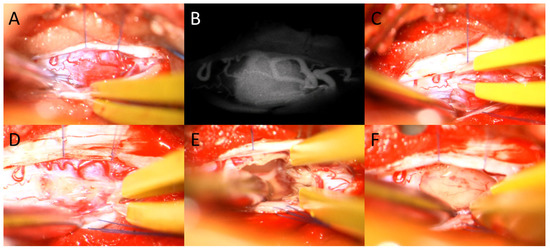

- Hao, S.; Li, D.; Ma, G.; Yang, J.; Wang, G. Application of intraoperative indocyanine green videoangiography for resection of spinal cord hemangioblastoma: Advantages and limitations. J. Clin. Neurosci. 2013, 20, 1269–1275. [Google Scholar] [CrossRef]

- Hojo, M.; Arakawa, Y.; Funaki, T.; Yoshida, K.; Kikuchi, T.; Takagi, Y.; Araki, Y.; Ishii, A.; Kunieda, T.; Takahashi, J.C.; et al. Usefulness of tumor blood flow imaging by intraoperative indocyanine green videoangiography in hemangioblastoma surgery. World Neurosurg. 2014, 82, E495–E501. [Google Scholar] [CrossRef]

- Tamura, Y.; Hirota, Y.; Miyata, S.; Yamada, Y.; Tucker, A.; Kuroiwa, T. The use of intraoperative near-infrared indocyanine green videoangiography in the microscopic resection of hemangioblastomas. Acta Neurochir. 2012, 154, 1407–1412. [Google Scholar] [CrossRef]

| Indocyanine green (ICG) angiography (N/%) | 22 (81.48%) |